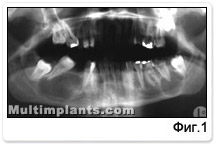

кстра орално - не се наблюдават изменения. Отварянето на устата бе в рамките на физиологичното. Интра орално - силно занемарена устна хигиена, наличие на зъбен камък и обилна плака. Множествен кариес. Лош дъх от устата. Гингивата, въпреки това бе спокойна, с розов цвят, плътна. Липсват 45 и 46 зъб, като прави впечатление силната патологична подвижност на 47 зъб и конвергенцията на короната му към дефекта, поради което разстоянието между ограничаващите зъби силно е намаляло. Установява се субтотално разрушена коронка на 37 зъб. При сондиране в кариозната кухина липсва болезненост. Рентгенологично на ортопантомография /фиг.1/ се вижда голяма киста в тялото на долната челюст вдясно, с овална форма, големият диаметър на която е 28 милиметра, а малкият 17 милиметра, обхващаща аспектите на 44 и 47 зъби. Linea albuginea - на места не се забелязва, но липсват клинични белези на екзацербация. 48 зъб - полуретиниран, а 47 и 44 зъби - с видимо незасегната пулпа. Вляво на 37 зъб се наблюдава радикуларна киста с правилна кръгла форма, с диаметър 16 милиметра. Размерите са изчислени въз основа на изследванията на Маджаров за увеличение размера на образа върху ортопантомография спрямо действителните размери. Linea albuginea - абсолютно отчетливо изразена, а 38 и 28 зъби са полуретинирани.